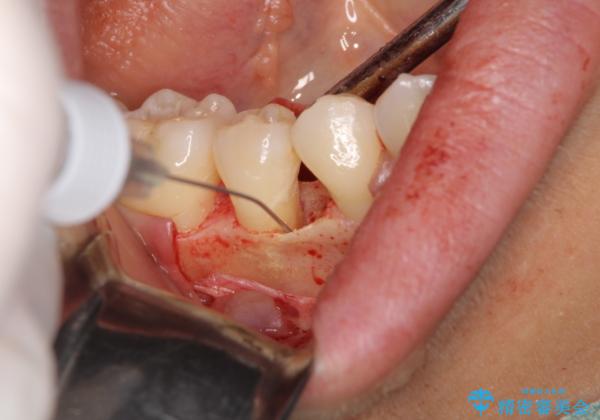

患者様は、他院で右下の歯を抜歯かもと言われました。全体の歯周病はなく、右下の1歯だけ骨が極端に減少していました(初診時歯周ポケット7mm。通常は3mm以下。)。その歯だけ咬合が強いことが原因と考えられたため、咬合を弱くする処置と減少した骨を再生する処置が必要になりました。

骨の再生治療手術をして10か月経過観察をしたのち、骨を平坦化する手術を行い、治療終了となりました。